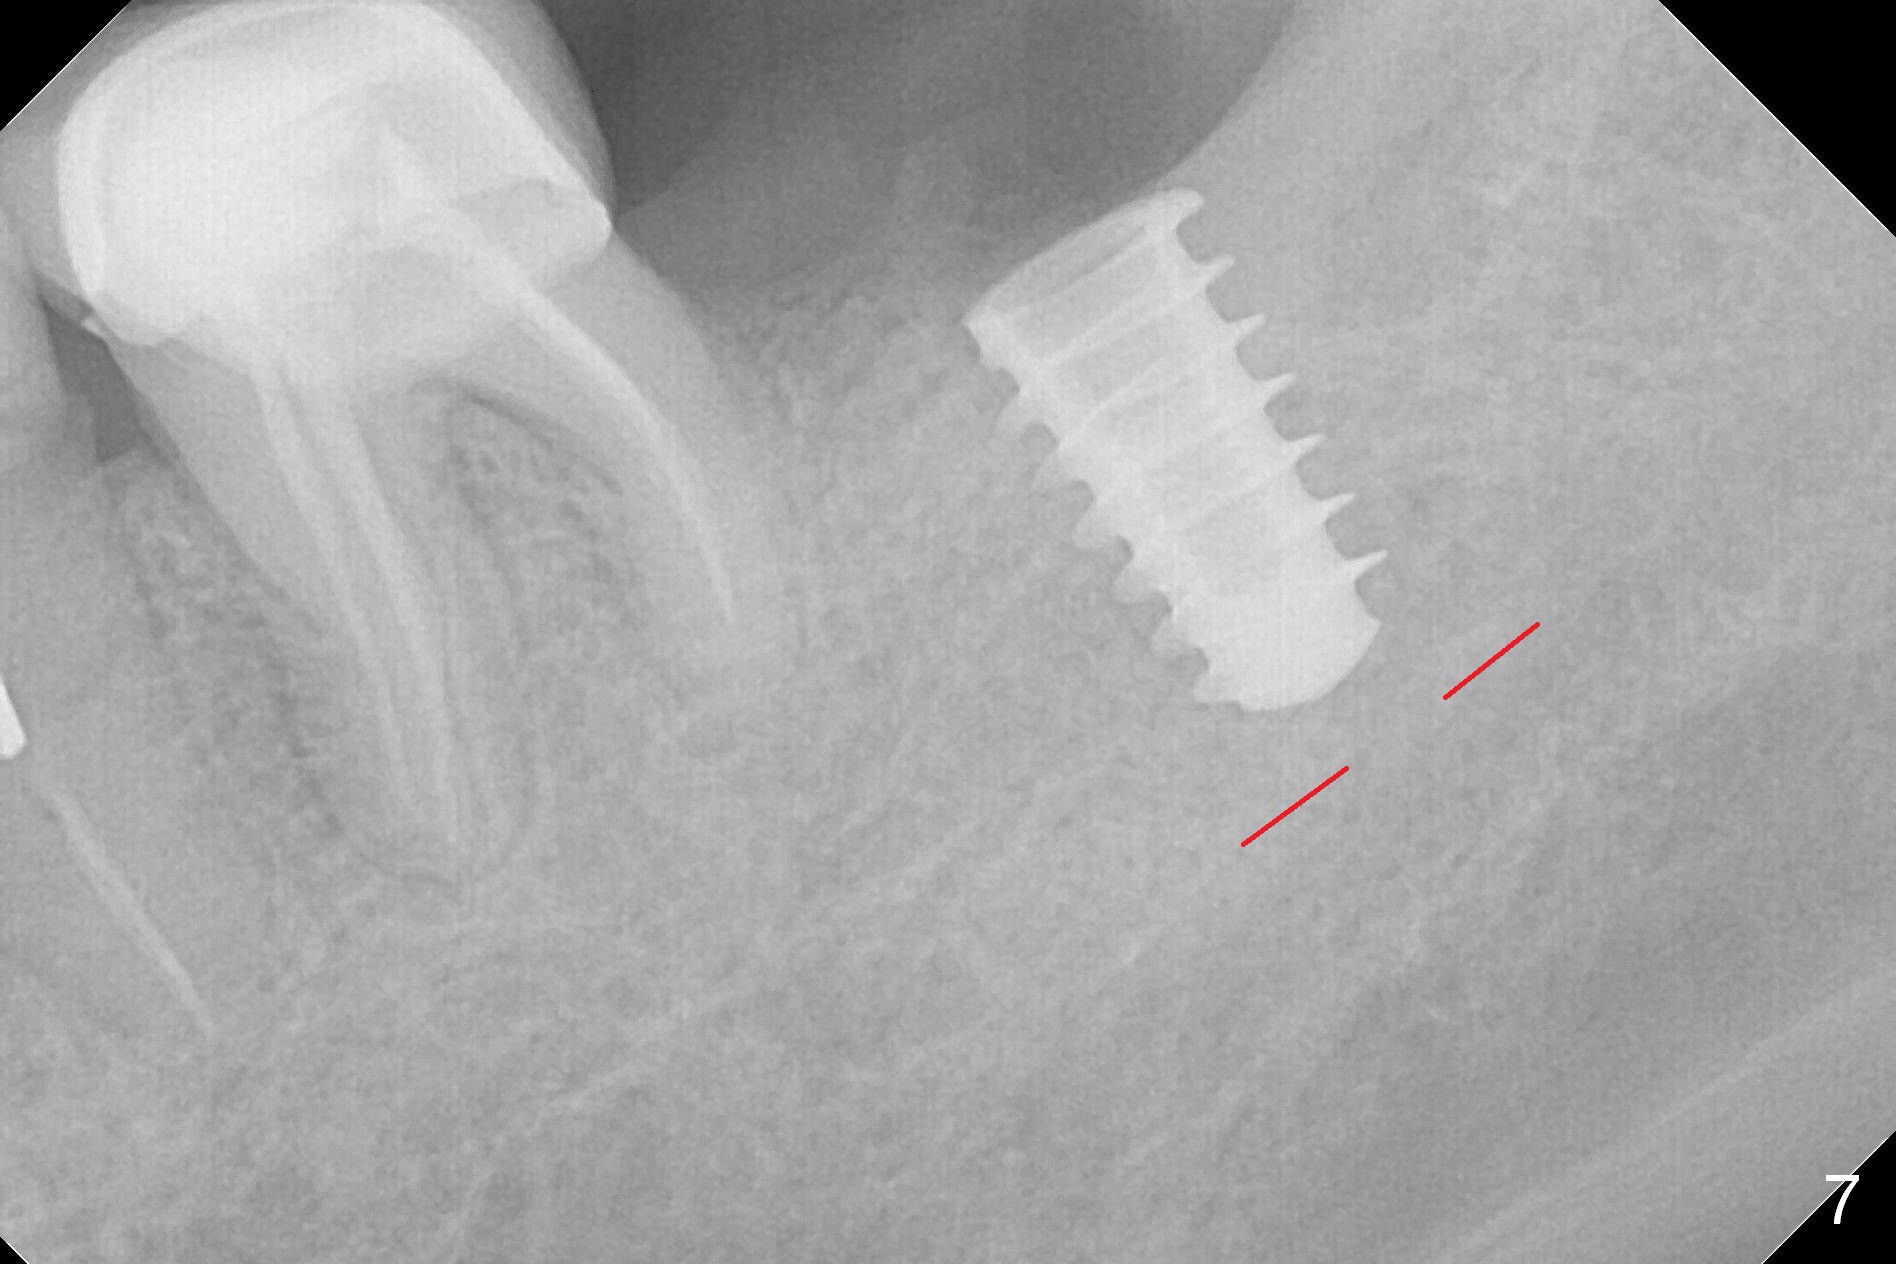

After 1.6 mm pilot drill (Fig.2) and 4.3 mm Magic Drill for 11 mm (gingival margin), a 4.5x11 mm dummy implant is placed with stability (Fig.3). Following Final Drill for 12/13 mm and 4.3 mm MD mesially, a 5x9 mm IBS implant is placed with 40 Ncm (Fig.4). Panoramic X-ray shows the placement is slightly supracrestal (Fig.5). In fact the implant is also placed slightly lingually. When the trajectory is changed, the implant loses stability. When a 5.5x9 mm implant is placed, no stability is achieved (Fig.6). After increase in osteotomy depth for 1-2 mm with MD 4.3 mm, the 5.5x9 mm implant barely obtains stability (~ 10 Ncm, Fig.7). Healing screw is placed. Osteogen plug is inserted in the distal portion of the socket; autogenous bone around the implant and Collagen plug to close the socket opening. Last suture and periodontal dressing are applied.